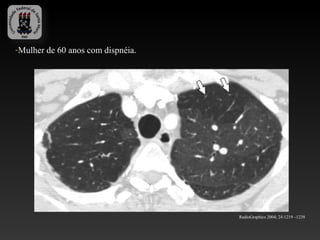

-Mulher de 60 anos com dispnéia.

RadioGraphics 2004; 24:1219 –1238